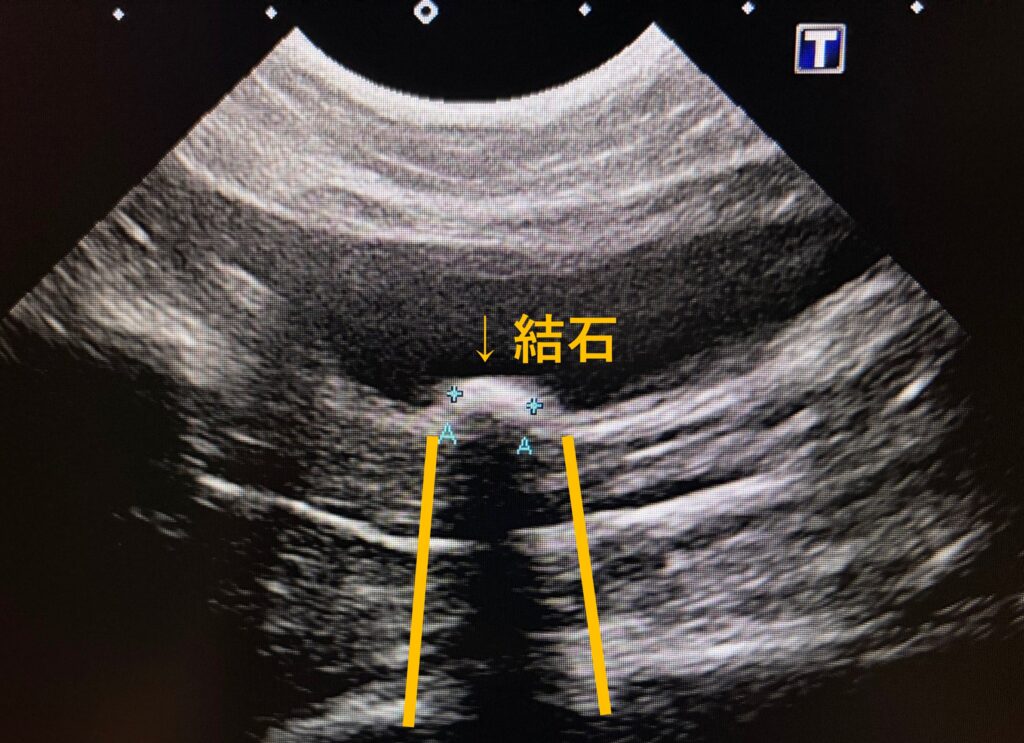

🐾尿石症ってどんな石?

おしっこの中にできる石には、種類があります。石の種類によって治療方法がまったく違うのがポイントです。

🧪どんな検査をするの?

- レントゲン・エコー検査

石の大きさや場所、膀胱の状態を確認